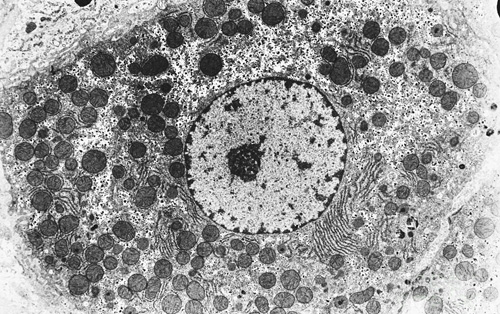

传统的转分化研究仅采用目标细胞的命运决定因子来诱导细胞类型的转变。邓宏魁研究组发现利用这一方法,仅仅过表达肝脏实质细胞的命运决定因子HNF1A、HNF4A和HNF6并不能获得功能成熟的人肝脏实质细胞,而只有在同时过表达功能成熟因子ATF5、PROX1和CEBPA的情况下,才能获得功能成熟的人肝脏实质细胞,且诱导效率超过90%。由这种新方法获得的细胞被命名为人诱导性肝脏实质细胞(human induced hepatocytes, hiHeps)。它具有成熟肝脏实质细胞的特征,特别是其药物代谢能力和肝脏毒素敏感性与新鲜分离的人成体原代肝脏实质细胞相当,为体外的药物高通量筛选提供了新的细胞来源。

这种hiHeps细胞首次在肝损伤的免疫缺陷小鼠上实现了高效重建肝脏功能。重建后的小鼠肝脏长期持续分泌高水平的人白蛋白,这种肝脏高度人源化的小鼠为人类肝炎病毒研究、药物代谢研究提供更加可靠的体内模型。研究组还发现hiHeps细胞长期移植后不会导致肿瘤的形成。更为重要的是,处于转分化中间状态的细胞具有极强的增殖能力,可在肝细胞功能成熟前扩增超过106倍,这意味着仅利用一滴血体积的人体细胞就可获得与人成体肝脏器官相当的人肝脏实质细胞数量,这一特征使得临床运用hiHeps进行细胞替代治疗极具应用前景。